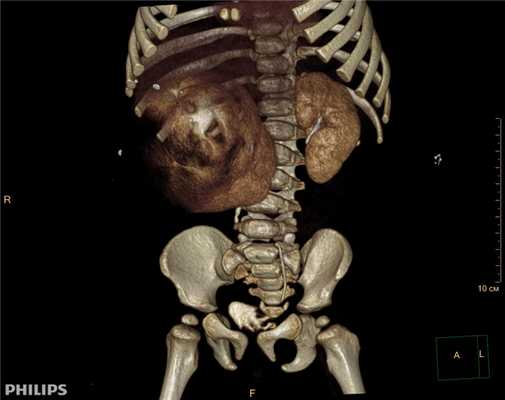

Компьютерная томография более детально дает информацию об анатомическом отношении опухоли к окружающим тканям и органам, позволяет оценить структуру опухоли (рис. 5).

Рис. 5. КТ нейрогенного образования забрюшинного пространства справа